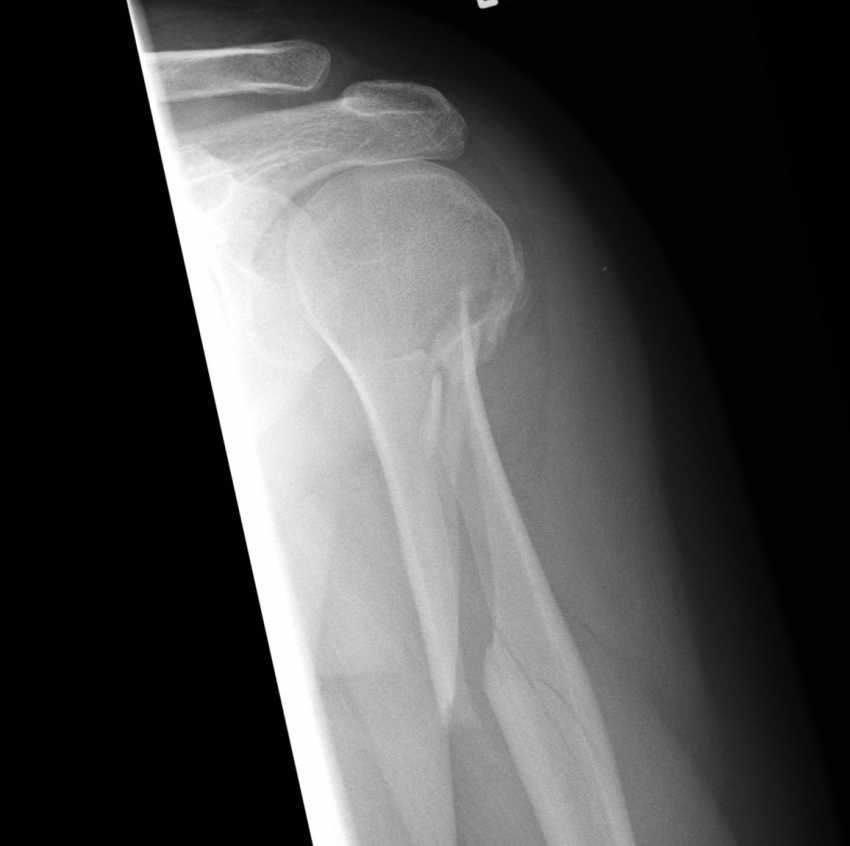

Impacted Fracture - एखादे हाड तुटते तेव्हा त्या हाडाचा हिस्सा दुसऱ्या हाडांमध्ये घुसण्याची स्थिती.